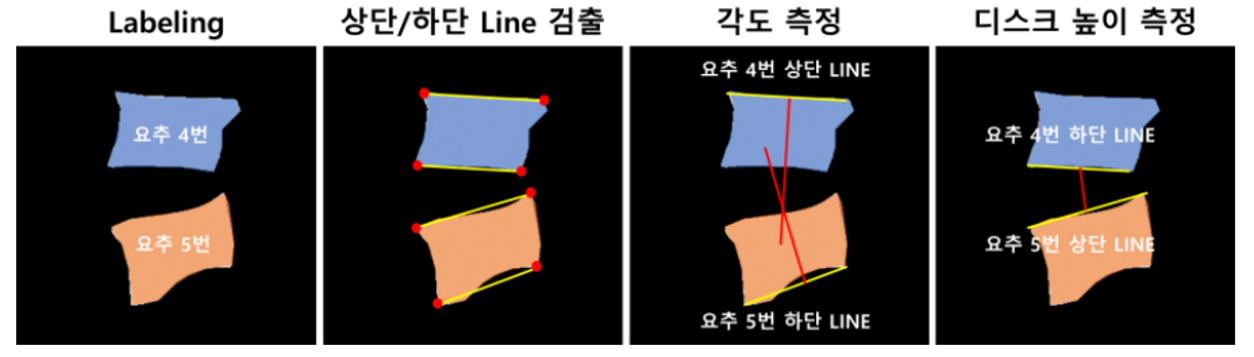

– Dice Coefficient Score 등데이터 비율 23776장 5944장 746장 - Predict 결과물의 각도와 거리 측정

- Predict mask 이미지의 외곽선을 추출하는 contour 기능을 이용하여 4번 5번 요추를 검출하고, 해당 데이터의 각도와 거리 측정

- 측정된 각도와 거리를 실제 측정값과 비교하여 Pearson-Correlation 분석

[요추 4, 5번 간의 디스크 높이 및 각도 측정]